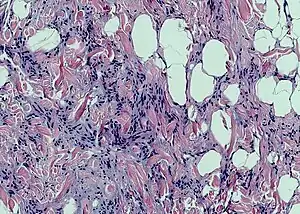

Histopathological examination of spindle cell lipoma